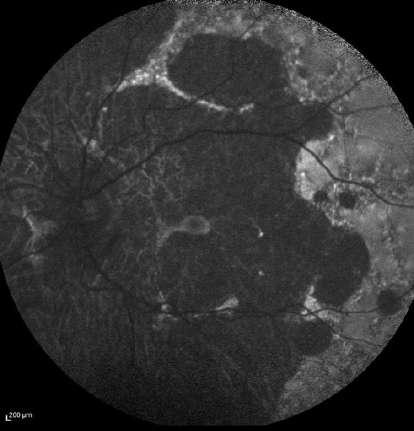

A la angiografía con fluoresceína (Fase activa)

ü Las áreas perfundidas demuestran una hiperfluorescencia en tiempos venosos con fuga tardía tanto a nivel tisular como vascular.

ü Las áreas isquémicas presentan una hipofluorescencia precoz con hiperfluorescencia por impregnación escleral tardía.

Clement F “Angiografía” Diagnóstico por la imagen en la retina, Sociedad Española de Retina y Vítreo, editado por Ignasi Jügens, Elservier, 2014, pp 41-66 A

Fase arterial

Fase A-V (arterio-venosa) Fase venosa

B C